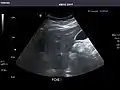

Left kidney

Kidneys: Right and left kidneys measure 11.5 cm and 12 cm in length respectively. No hydronephrosis. Small left lower pole kidney cyst.